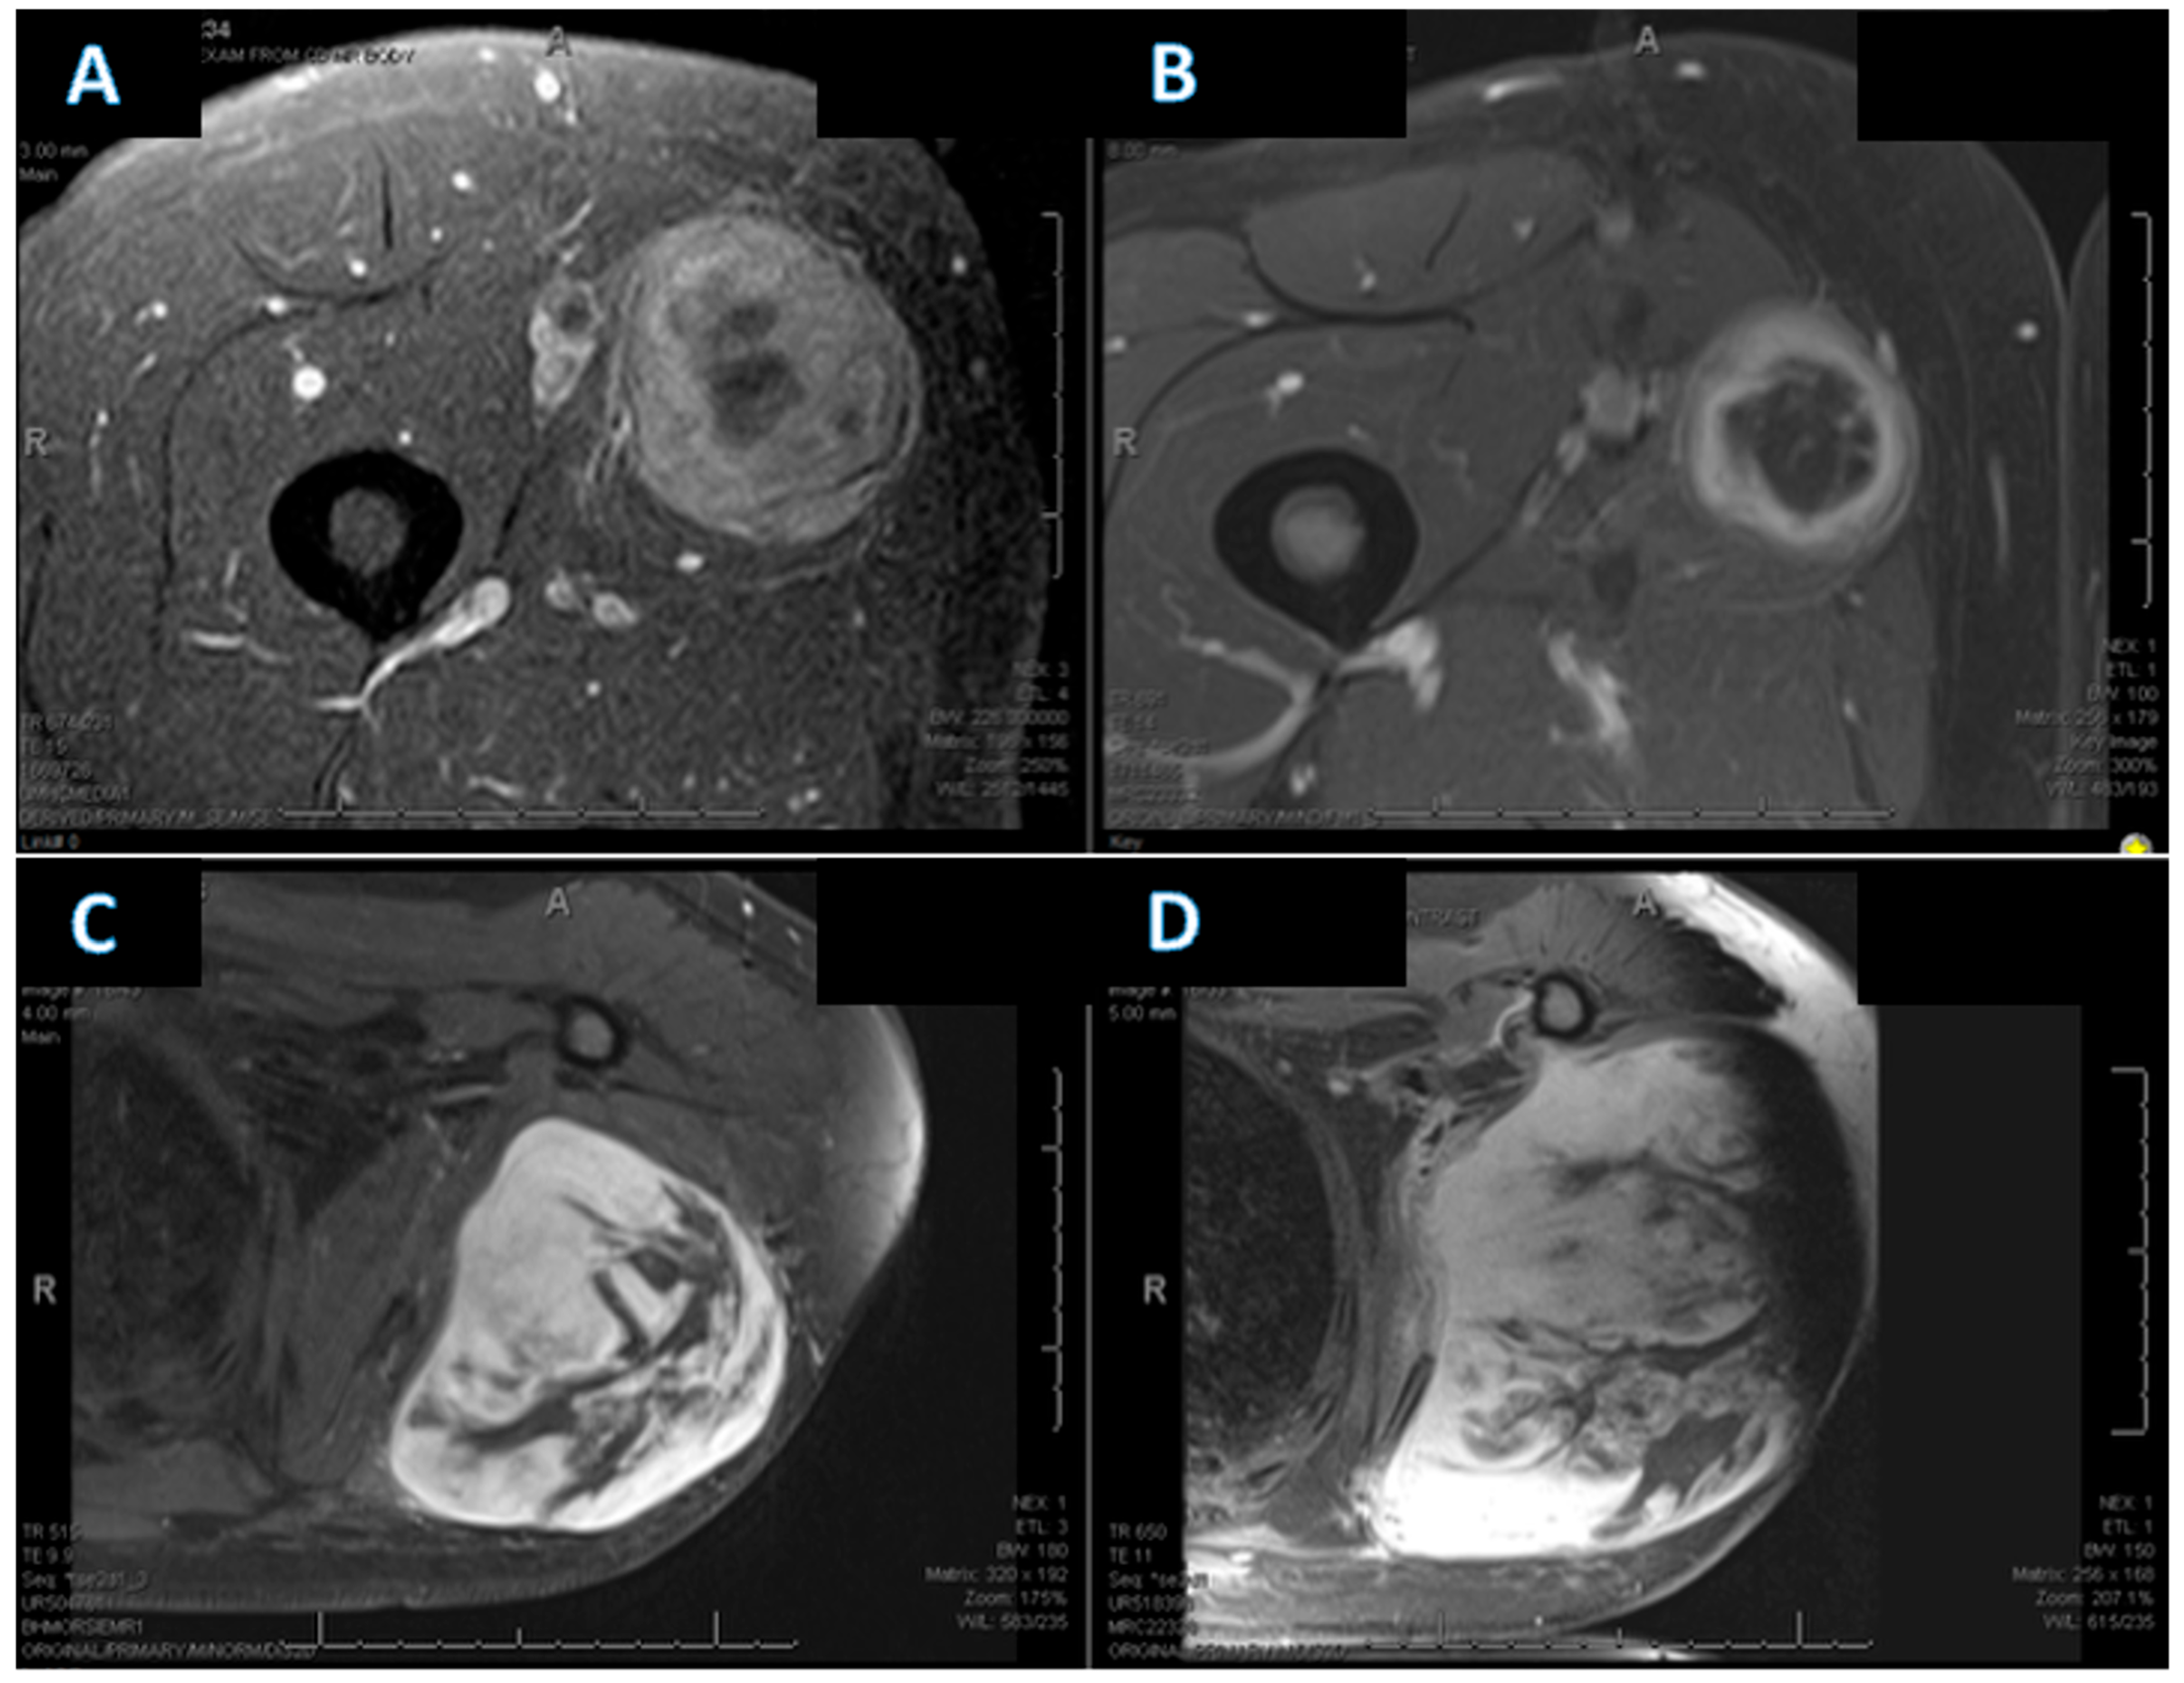

Representative pre- and post-treatment MRI examples illustrating changes in tumor necrosis are shown in Figure 3, including one case with a marked increase in necrosis (Δ necrosis 47.5%) and one case with no change in necrosis (Δ necrosis 0%).

Figure 3. Representative MRI examples illustrating evaluation of changes in tumor necrosis following neoadjuvant chemotherapy: (A,B) Example demonstrating a substantial increase in necrosis (Δ necrosis 47.5%). (A) Baseline MRI (MRI-1) showing an estimated necrosis of 25–50%. (B) Post-neoadjuvant MRI (MRI-2) demonstrating increased necrosis, estimated at 75–95%. (C,D) Example demonstrating no change in necrosis (Δ necrosis 0%). (C) Baseline MRI (MRI-1) with estimated necrosis of 25–50%. (D) Post-neoadjuvant MRI (MRI-2) with unchanged estimated necrosis (25–50%). All images were obtained from the electronic medical record, and representative axial slices were selected by a dedicated musculoskeletal radiologist.